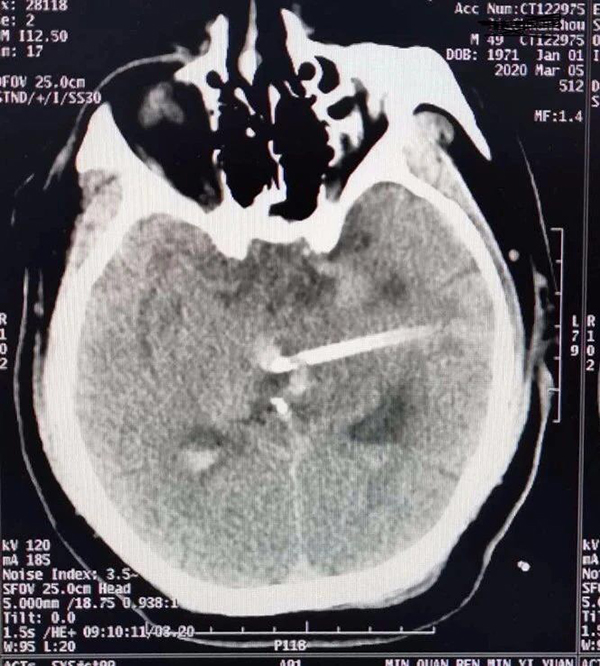

王某,男,49岁,以“右侧肢体无力伴失语1小时”入院,颅脑CT示:左侧丘脑出血破入脑室、梗阻性脑积水,入院时血9压185/110mmhg,深昏迷,GCS 3分,双侧瞳孔左=右,直径约2mm,对光反射消失,颈强,双侧巴士征阳性。

术前CT

术后经尿激酶冲洗后4日复查CT